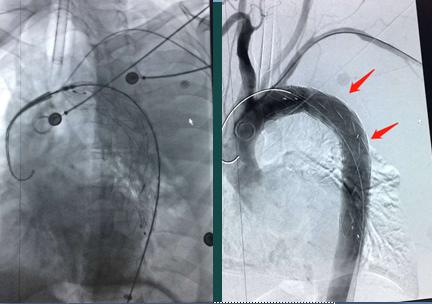

介入科和心血管科4位主任都早已在介入导管手术室就位,

支架植入,成功封堵!(第3道关卡)

生命危险解除!